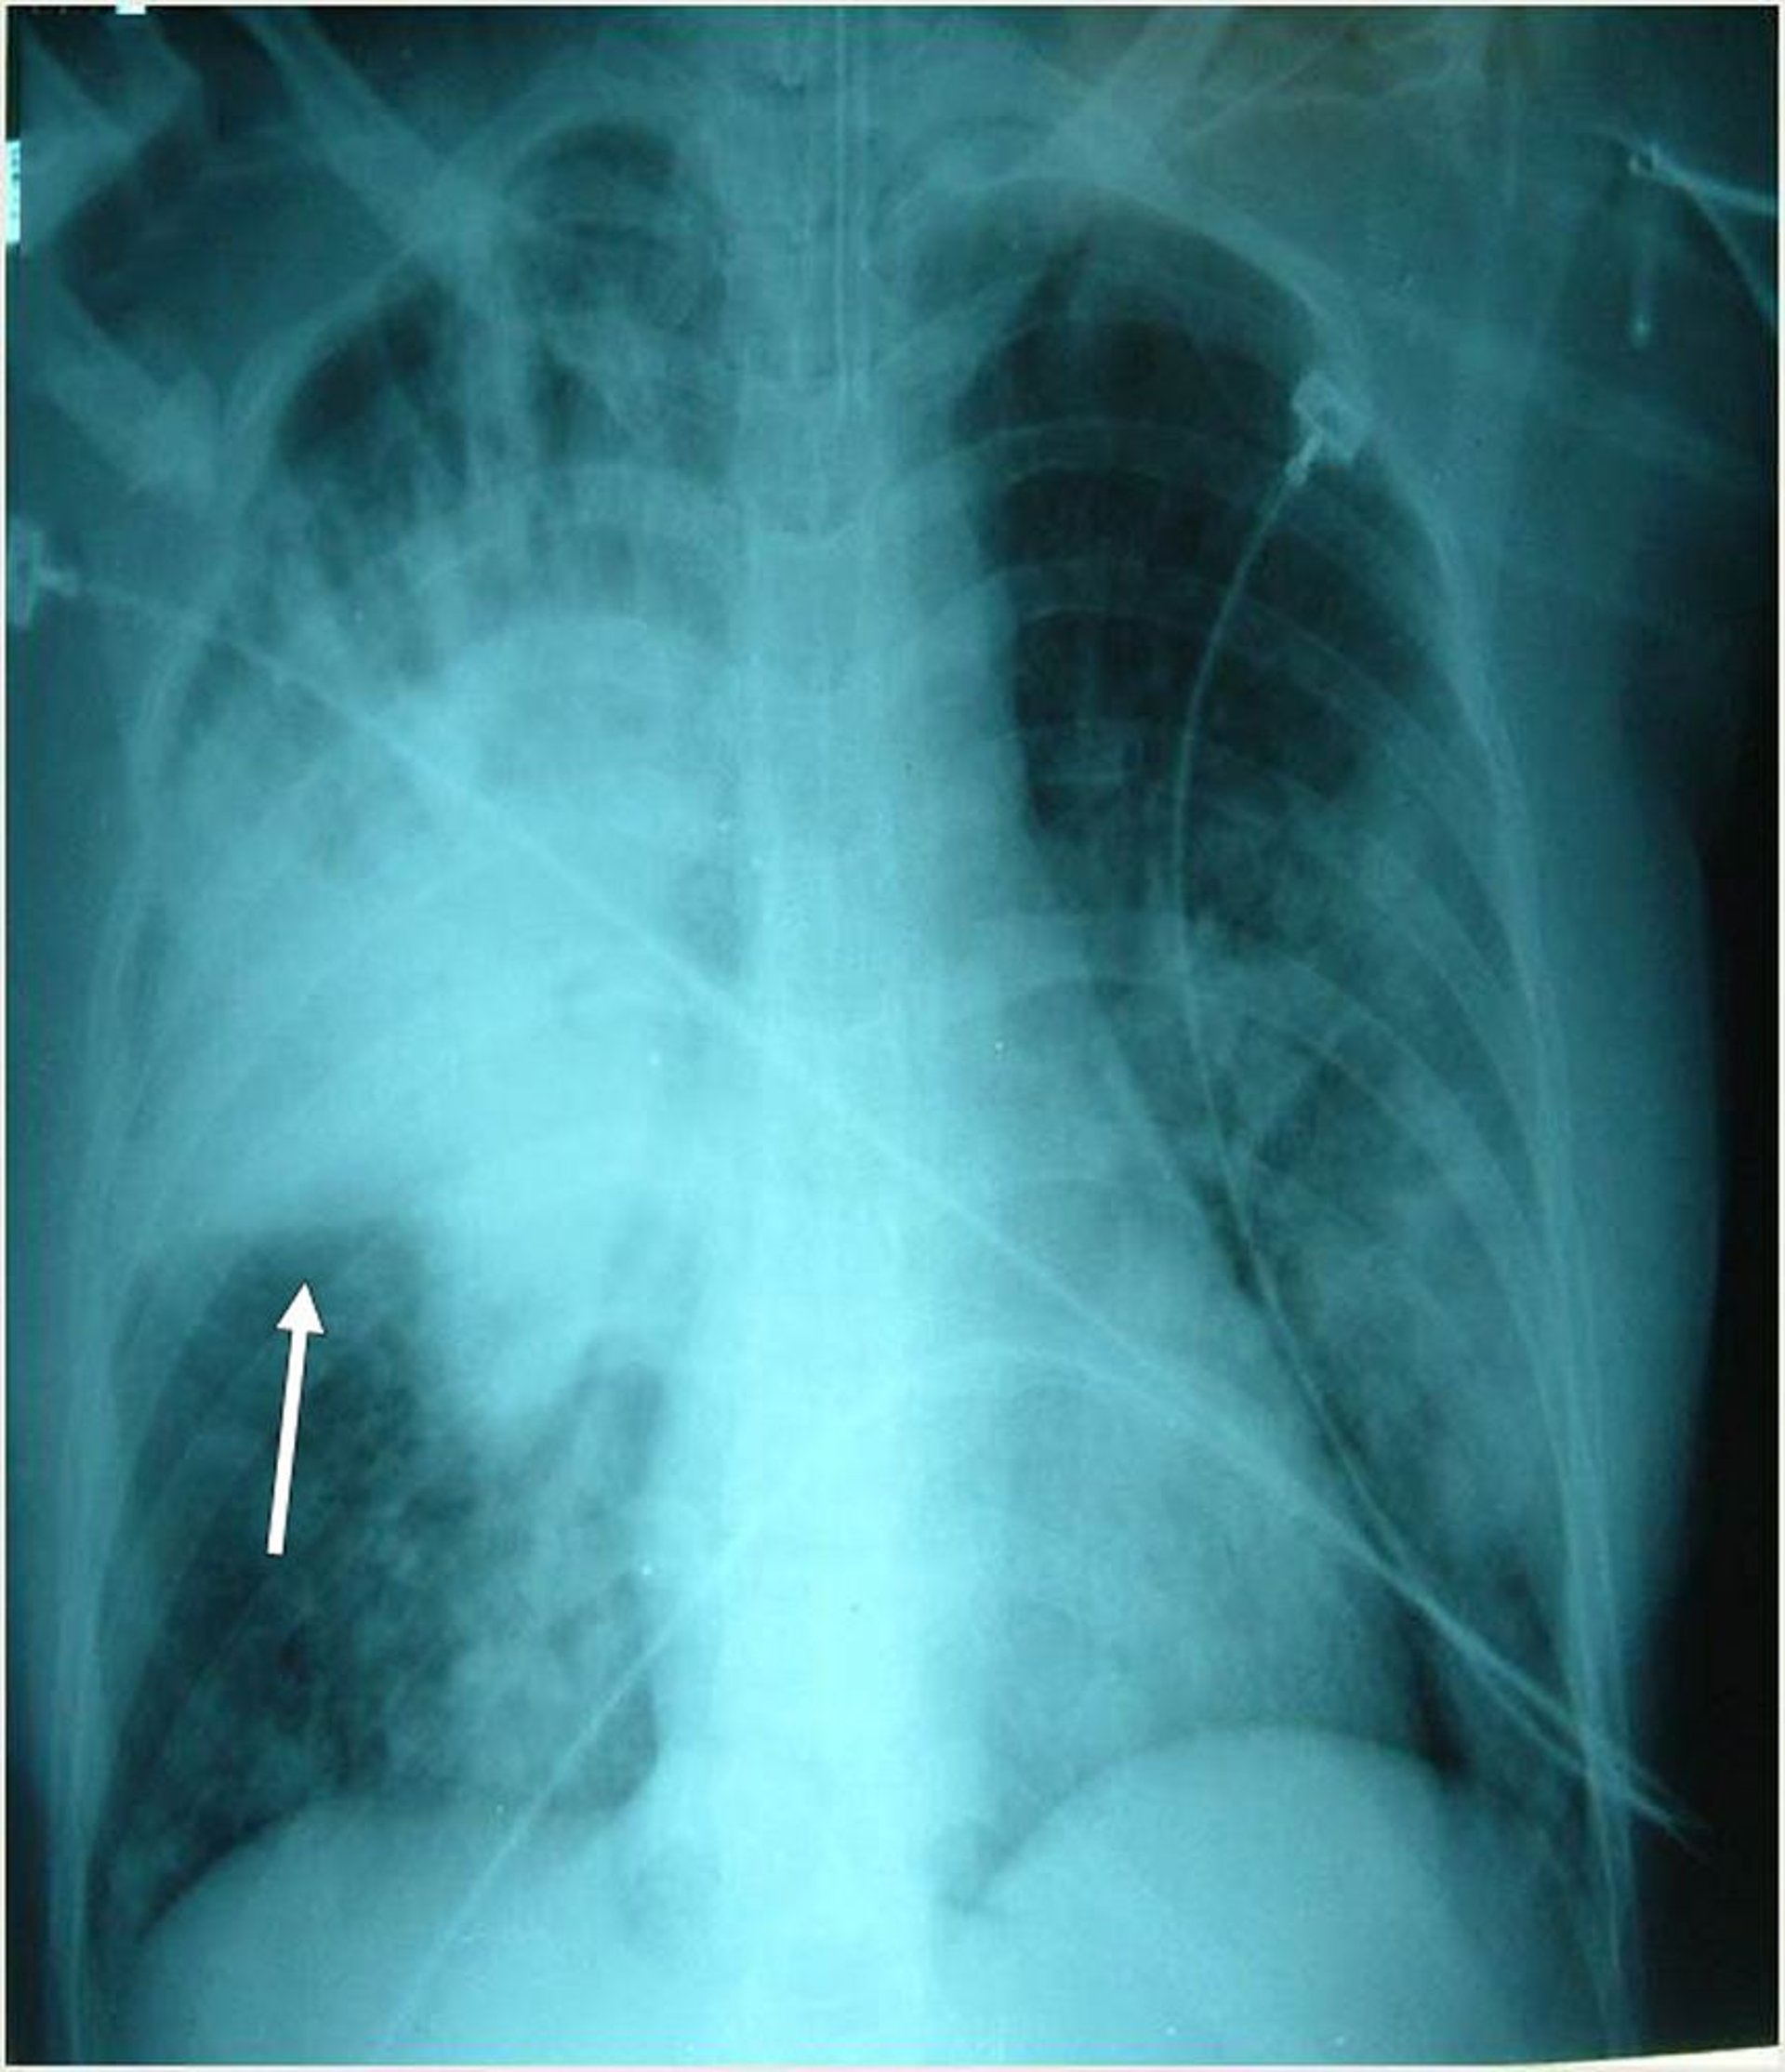

Ce patient intubé a de multiples infiltrats bilatéraux, principalement dans le lobe supérieur droit. La flèche indique la scissure horizontale droite.